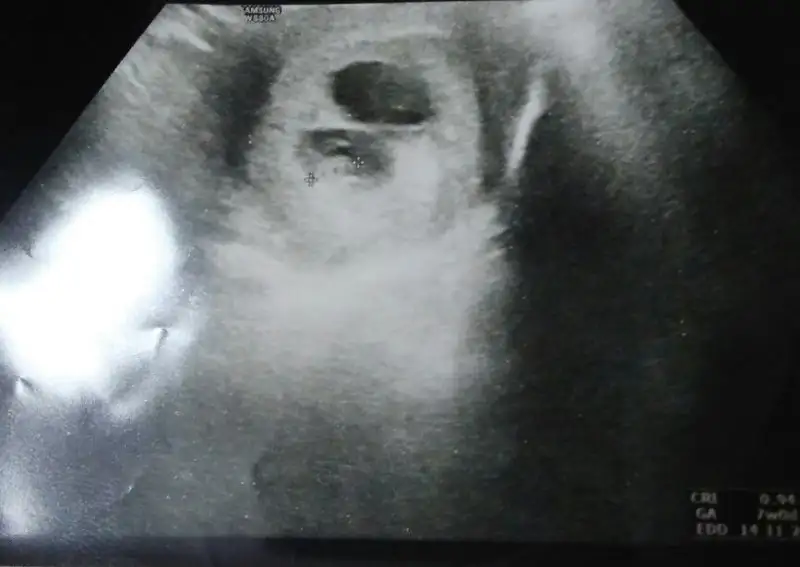

gün gecmiyor sabirsizliktan gebercem. 8 haftalik usg yukledim.

Kızlar banada yorum yapın 8 haftalık ramzi teorisine göre yorumlanınca ne oluyor cinsiyet karından bakıldı

• 8AEFAB3F-C91D-41C4-8C11-28BA1880028A.webp

22,7 KB · Görüntüleme: 157